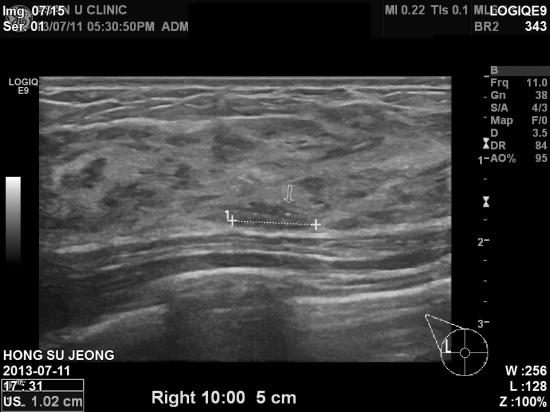

검진센타에서 유방촬영상 중등도의 위험의 미세석회화가 있어

내원한 40세 여자분이십니다.

본원에서 유방초음파를 다시 시행하여 조직검사시행 상피내암을 진단 받으셨읍니다.